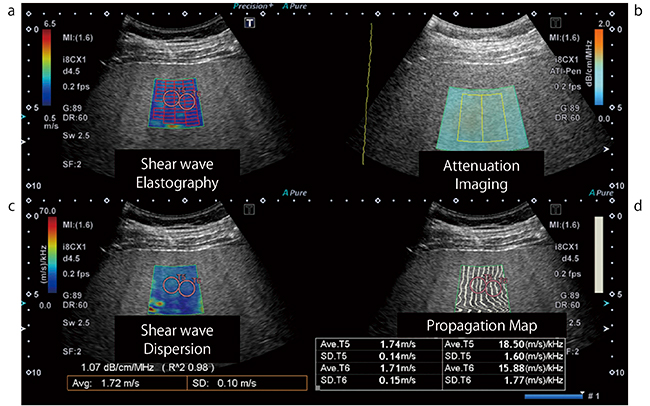

図1 SWE,SWD,ATI表示例

1回の収集でSWEとATIの情報を得ることが可能。aがSWE,bがATI,cがSWD,dがPropagation map for SWE。SWEのカラーROI内に表示されている赤い枠がMeasurement Area Detection表示,その計測結果はc下部の黄色枠内に表示されている。その計測結果の上に表示されているのが,推定された減衰係数の結果。d下部に表示されている数値は,SWE,SWDの計測結果表示。